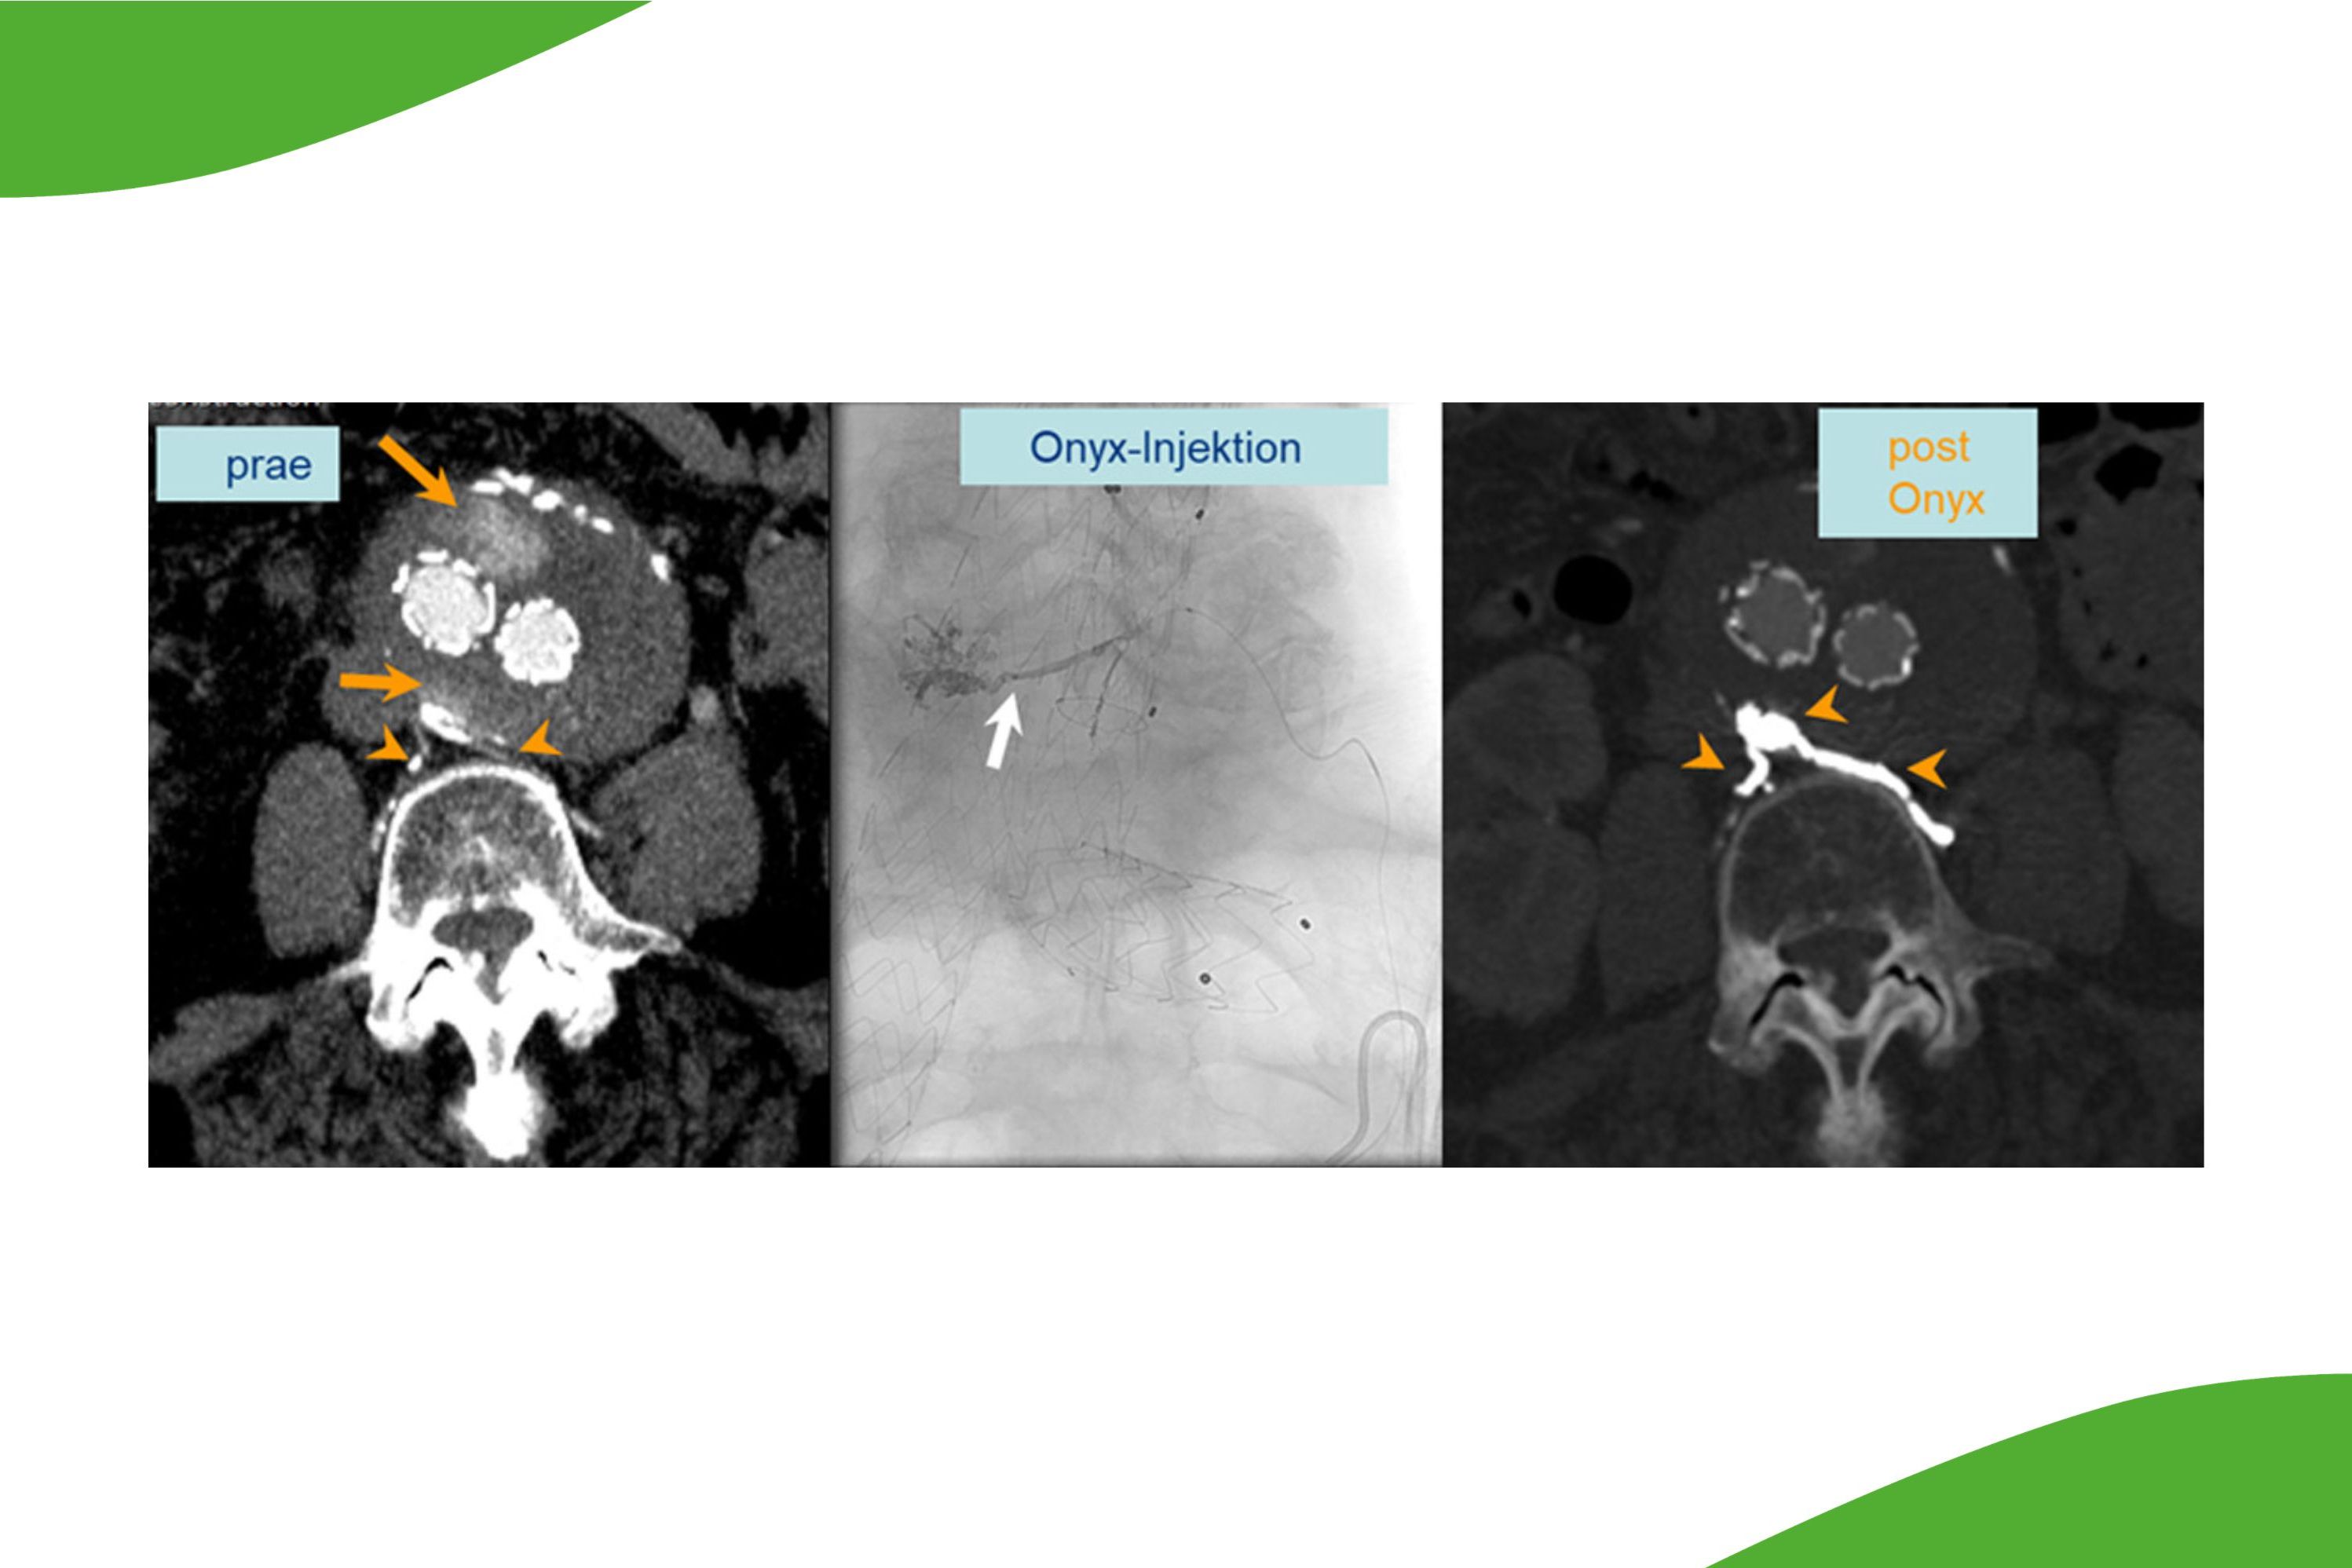

Eine spezielle Expertise besteht in der Durchführung von ggf. erforderlichen weiteren Behandlungen nach Aortenstentgraft (EVAR bzw. FEVAR). In seltenen Fällen können Undichtigkeiten entstehen oder über kleine Seitenäste kann auch eine Restdurchblutung des Aneurysmasackes entstehen (sogenannte Endoleaks), welche dann zum Teil behandelt werden müssen. Durch die Verfügbarkeit verschiedenster Materialien auch von kleinsten Kathetern, welche ansonsten im Bereich der Neuroradiologie und für Interventionen im Gehirn oder im Rückemarksbereich eingesetzt werden, kann nun auch über kleinste Kollateralen der Zufluss aufgesucht werden und entweder mit Coils oder Plugs behandelt werden oder aber auch Zuflüsse und der Aneurysmasack selber mit speziellen Embolisaten ausgekleidet werden (siehe Abbildung).

EVAR Repair (links) bei sog. Endoleak u.a. über Lumbalgefässe (Pfeilspitzen) und großer Kontrastmittelansammlung im Aneurysmasack (orange Pfeile links) mit deutlichem Größenwachstum des Aneurysmasackes trotz Endograft (extern vor mehreren Jahren). Onyx-Injektion (Mitte) mit Mikrokatheter am Aneurysmasack (weißer Pfeil), Okklusion des Endoleaks und beider Lumbagefässmündugnen mit dem Onyx-Cast über eine Mikrokatheterposition. In der CT Kontrolle ist das Embolisat in den ehemaligen Zuflüssen gut erkennbar.